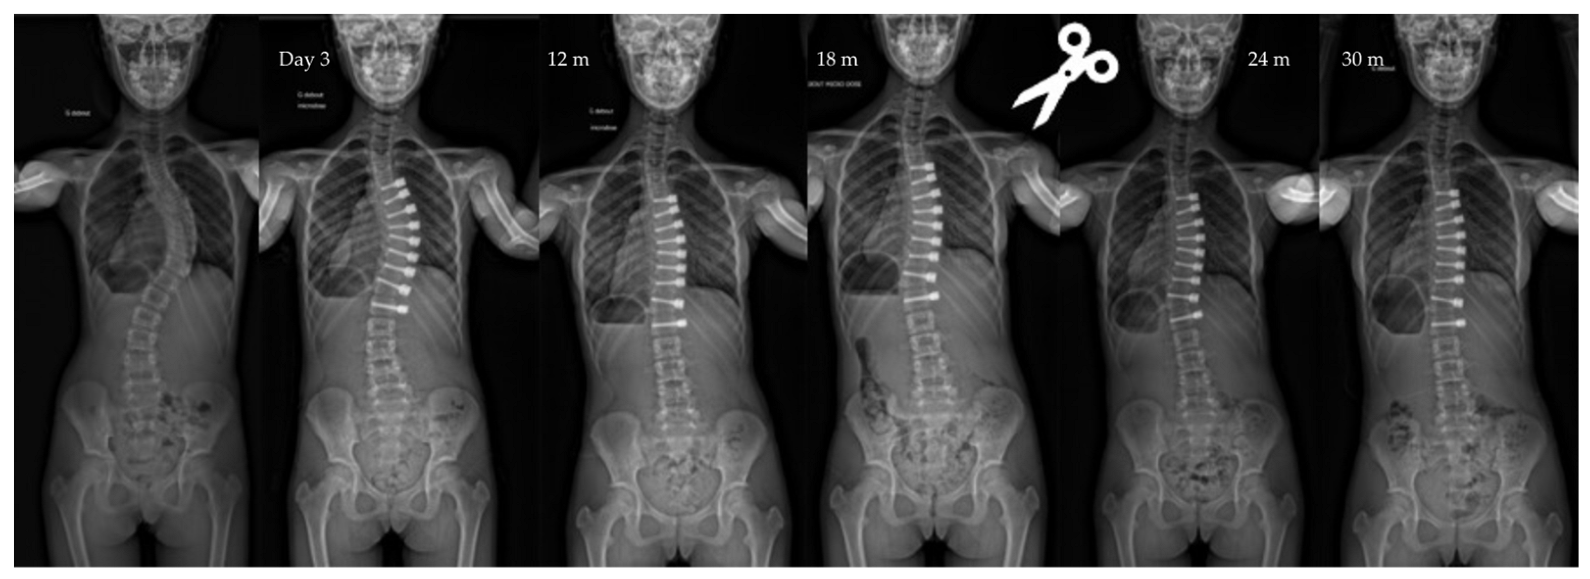

| Pre-op | Post-op Day 3 | Post-op 1y | Last f/u | p-Value | |

|---|---|---|---|---|---|

| Major curve | 49°(8,9°) | 27°(12°) | 22°(12°) | 19°(14°) | <0.01 |

| Secondary curve | 27°(14°) | 23°(15°) | 22°(11°) | 17°(10°) | <0.01 |

| Instrumented curve | NA | 26°(11°) | 23°(10°) | 20°(14°) | <0.01 |

| Kyphosis (T1–T12) | 20°(13°) | 23°(13°) | 25°(12°) | 24°(14°) | 0.06 |

| Lordosis (L1–L5) | 36°(12°) | 32°(13°) | 40°(7°) | 40°(8°) | 0.07 |

| Overcorrection | 10 (11%) | 10 right thor. | 5 tether release | Between 1,5, and 2 y po |

| Tether breakage | 2 (2%) | Lumbar | - | 2 y po |

| Cranial screw slippage | 6 (7%) | Thor. | - | 18 months po |